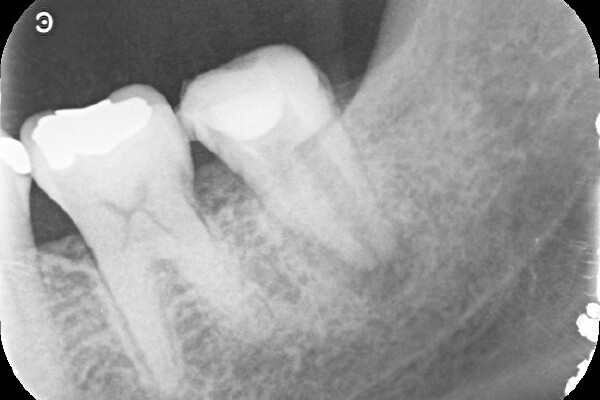

①自覚症状なし・歯肉にサイナストラクト(排膿路)あり

②初診時レントゲン解説

・歯根周囲に透過像(黒い影)あり

・遠心根根管充填:アンダー

根管治療そのものは、2回で終了し、水酸化カルシウム貼薬し経過観察(患者様希望のため)

約2か月後、根尖透過像の縮小を確認し根管充填(MTA使用)。

レントゲン解説:4根管すべてに根管充填が密にされていることを確認できる

透過像は消失し、明らかな骨形成を認める。(黒い影の消失)